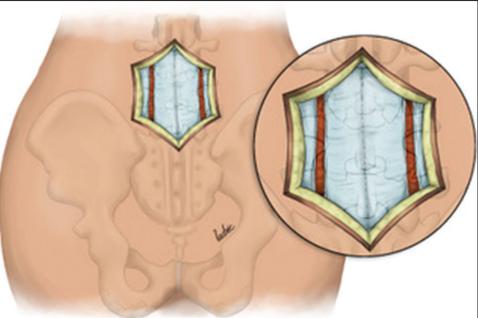

4.

Dissectionandexposure: (a)subcutaneous tissuedissected,(b)thoracolumbarfascia incised,(c)paraspinalmusclesdetached subperiosteallyfromspinousprocessand lamina,(d)facetsand transverseprocesses exposed(andserveasvitallandmarksfor fusion),(e)ligamentumflavumcompletely removedforeachtreatedlevel